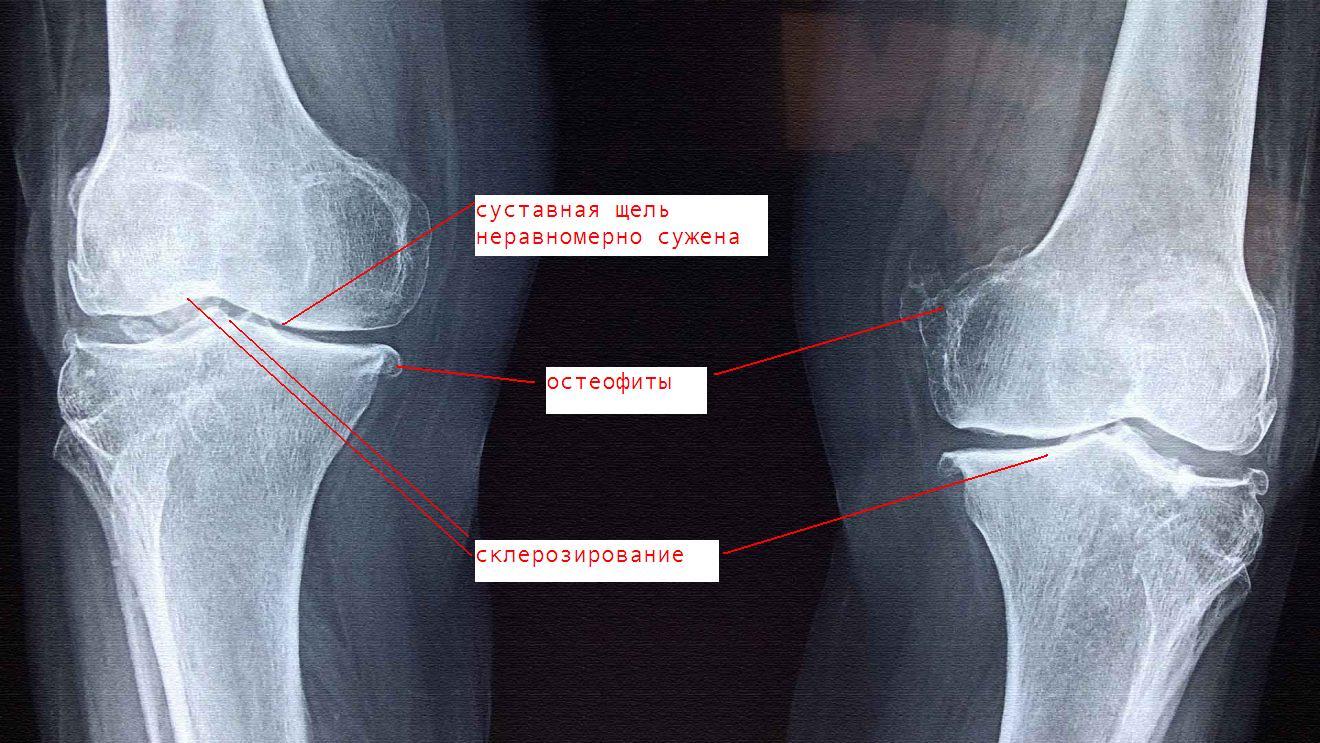

Заболевания и медицинские снимки: Жидкость в коленной чашечке

Раздел: Галерея прозрений